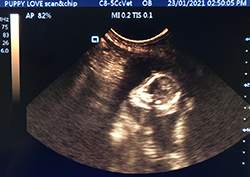

Mobile Ultrasound Pregnancy Scanning and Microchipping Services

Puppy Love scan and chip